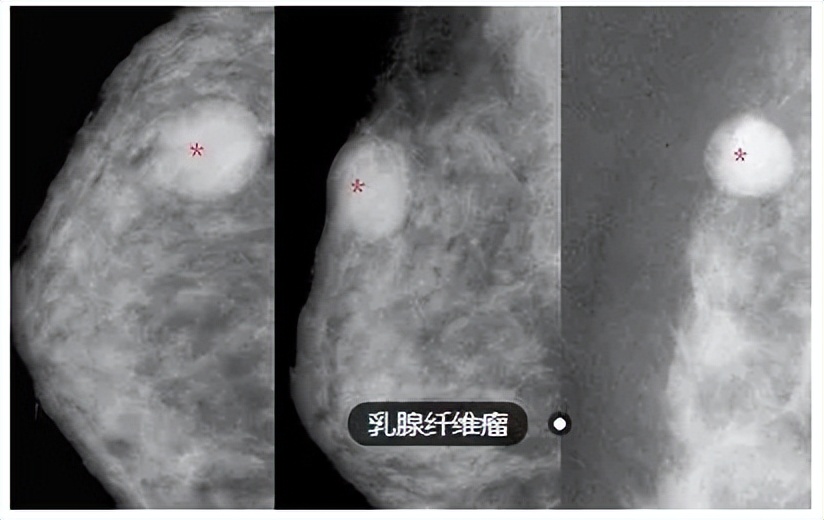

什么是乳腺纤维瘤?

乳腺纤维瘤是一种发病于乳腺的良性肿瘤性疾病 ,该疾病的发生会导致女性患者朋友的乳房出现边界清晰以及光滑的无痛性肿块。

按照患者的病情,可以将乳腺纤维瘤分为 单纯型纤维腺瘤、少年型纤维腺瘤、巨大纤维腺瘤以及复杂型纤维腺瘤。